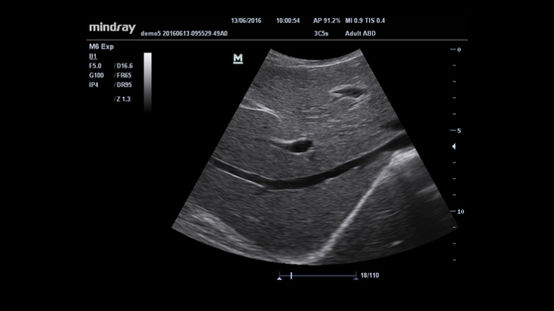

Sistema de ultrasonido

M6

Con la idea de un cuidado médico al alcance de todos siempre en mente, Mindray ha lanzado su nuevo M6, el equilibrio ideal de capacidad y tamaño para llevar a cabo un diagnóstico fiable en la propia cabecera de la cama.